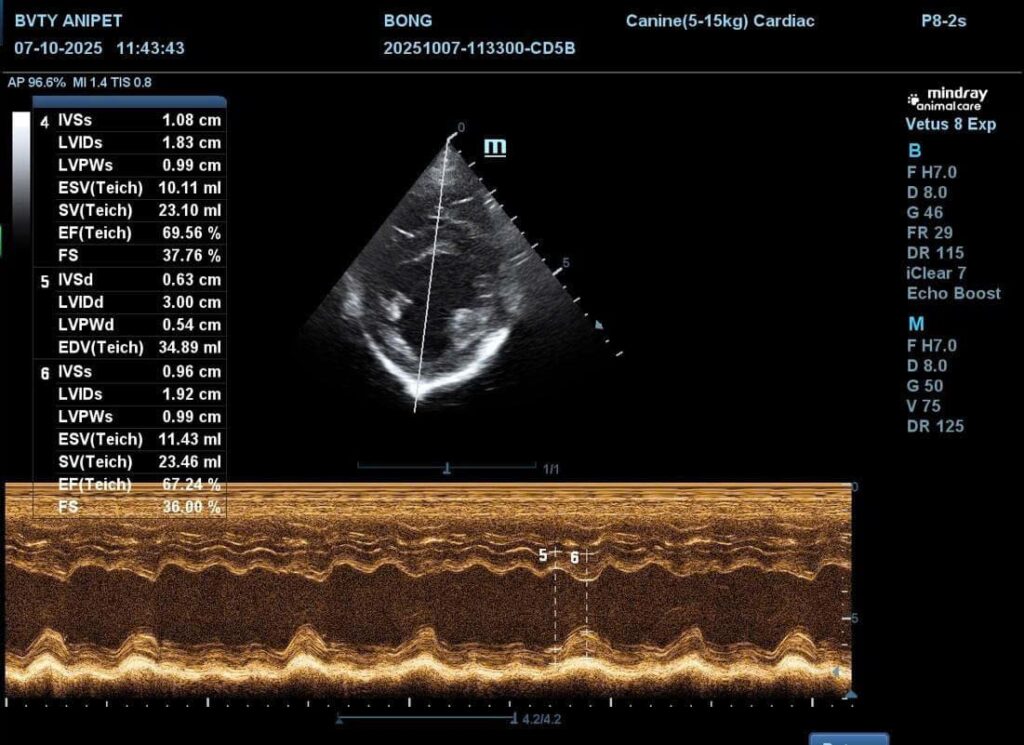

Siêu âm tim và chụp X-quang

Tiếp đến, bác sĩ sẽ tiến hành siêu âm tim và chụp X-quang tim phổi nhằm đánh giá cấu trúc tim, độ dày thành tim và tình trạng phổi. Siêu âm tim giúp quan sát trực tiếp sự co bóp của tim, trong khi X-quang cho biết tim có bị phì đại hay dịch có ứ đọng ở phổi không.

Hai phương pháp này hỗ trợ phát hiện sớm các bệnh lý như suy tim sung huyết hoặc bệnh van tim ở chó mèo.